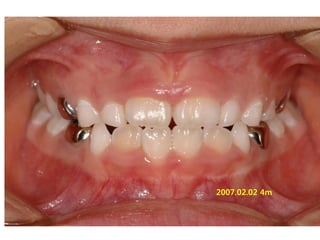

1999.11.24 /F

C.C

• Ant. crossbite, crowding

Dx

• Incorrect tongue posture and mentalis action

Goal

• Establish normal tongue posture and swallowing

pattern

2006.09.07

2006.10.27 Start T4K

2007.02.02 4m